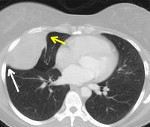

Доброкачественные опухоли плевры обычно выявляются при рентгенологическом исследовании (полипозиционной рентгенографии грудной клетки, рентгеноскопии легких). На рентгенограммах определяется полукруглая или полуовальная гомогенная тень с четкими очертаниями, прилежащая своим широким основанием к тени ребер, реже — диафрагмы либо средостения. При рентгеноскопии легких хорошо видно, как опухоль, исходящая из париетальной плевры, при дыхании смещается вместе с ребрами. Структура ребер, как правило, не изменена прилежащими к ним доброкачественными опухолями плевры.

Уточняющая роль в диагностике опухолей плевры отводится КТ и МРТ легких, УЗИ плевральной полости. Под контролем КТ или УЗИ проводится пункционная биопсия плевры с последующим исследованием биоптата; при наличии экссудата выполняется плевральная пункция. При недоступности опухоли плевры для трансторакальной биопсии прибегают к диагностической торакоскопии (плевроскопии).